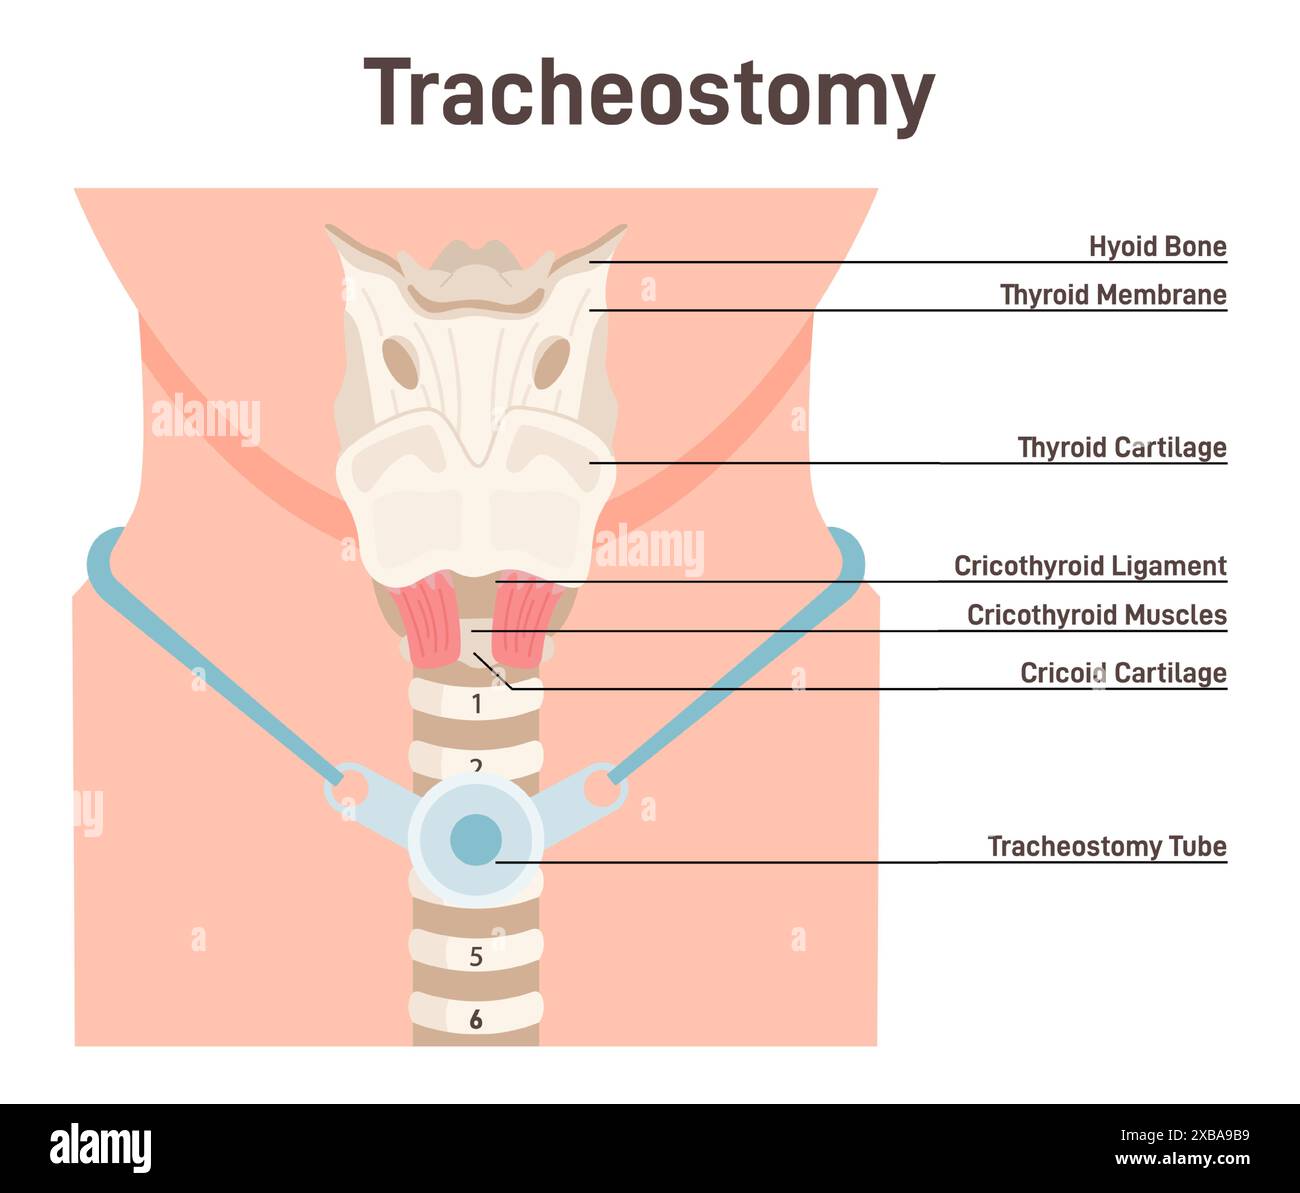

Tracheostomy. Tracheal surgery neutralise airway obstruction. Plastic cannula with inflatable cuff. Trachea anatomy. Flat vector illustration Stock Vectorhttps://www.alamy.com/image-license-details/?v=1https://www.alamy.com/tracheostomy-tracheal-surgery-neutralise-airway-obstruction-plastic-cannula-with-inflatable-cuff-trachea-anatomy-flat-vector-illustration-image609350989.html

Tracheostomy. Tracheal surgery neutralise airway obstruction. Plastic cannula with inflatable cuff. Trachea anatomy. Flat vector illustration Stock Vectorhttps://www.alamy.com/image-license-details/?v=1https://www.alamy.com/tracheostomy-tracheal-surgery-neutralise-airway-obstruction-plastic-cannula-with-inflatable-cuff-trachea-anatomy-flat-vector-illustration-image609350989.htmlRF2XBA9B9–Tracheostomy. Tracheal surgery neutralise airway obstruction. Plastic cannula with inflatable cuff. Trachea anatomy. Flat vector illustration